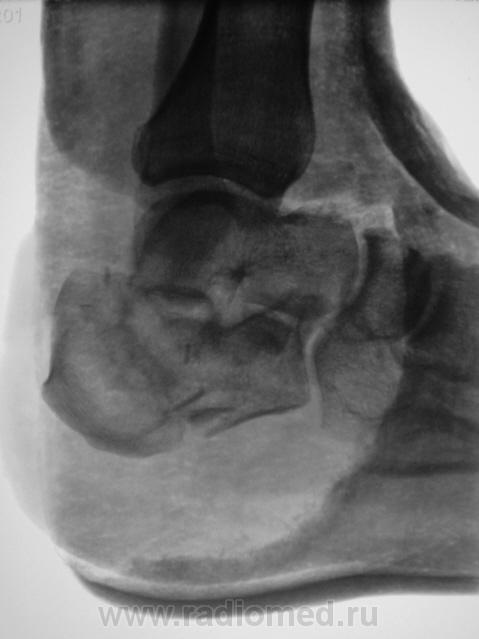

Лечение состояло из "множества рентгенов" и гипса. Срок - 5 месяцев.

Сейчас думают об остеомиелите.

Контуры пяточной кости относительно четкие, разрежение структуры пяточного бугра, в проекции перелома уплотнение структуры кости( имею в виду последние снимки).Клиника остеомиелита есть?

Во-первых, деформация пяточной кости; во-вторых, отсутствие консолидации, через некоторое время и ложный сустав сформируется. Неоднородное уплотнение костной структуры в теле кости может быть обусловдено как остеомиелитом, так и перераспределением нагрузки.

Признаков остеомиелита не вижу, только консолидир перелом с неуд стоянием отломков.